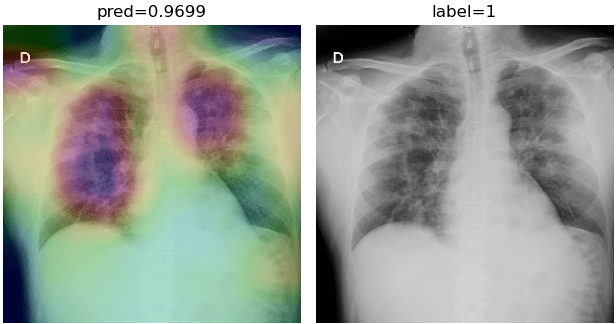

To overcome the aforementioned issues and force the model’s attention to the correct regions of interest (ROIs), we introduce the COVID-CXNet. Our model is initialized with the pretrained weights from CheXNet. A dataset of 3,628 images, 3,200 normal CXRs and 428 COVID-19 CXRs, are divided into 80% as training-set and 20% as test-set. Batch size is set to 16, rather than 32 in previous models, regarding memory constraints. Grad-CAMs of the COVID-CXNet for random images are plotted in Fig. 15.

Figure 15: Grad-CAM visualization of the proposed model over sample cases

More Grad-CAMs are available in Appendix A. Heatmaps are more accurate than previous models, while an accuracy of 99.04% and an f-score of 0.96 are achieved. Table 3 is the confusion matrix of the proposed model.